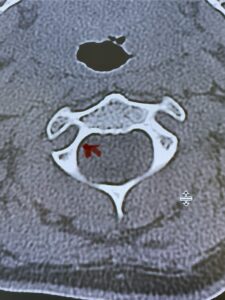

Fig. 4b: Axial T2-weighted cervical MRI demonstrating severe spinal cord compression from atlanto-axial instability (red arrow)

Fig. 6c: Axial cervical CT scan demonstrating a very thin right C2 isthmus (red arrow) compared to left side.